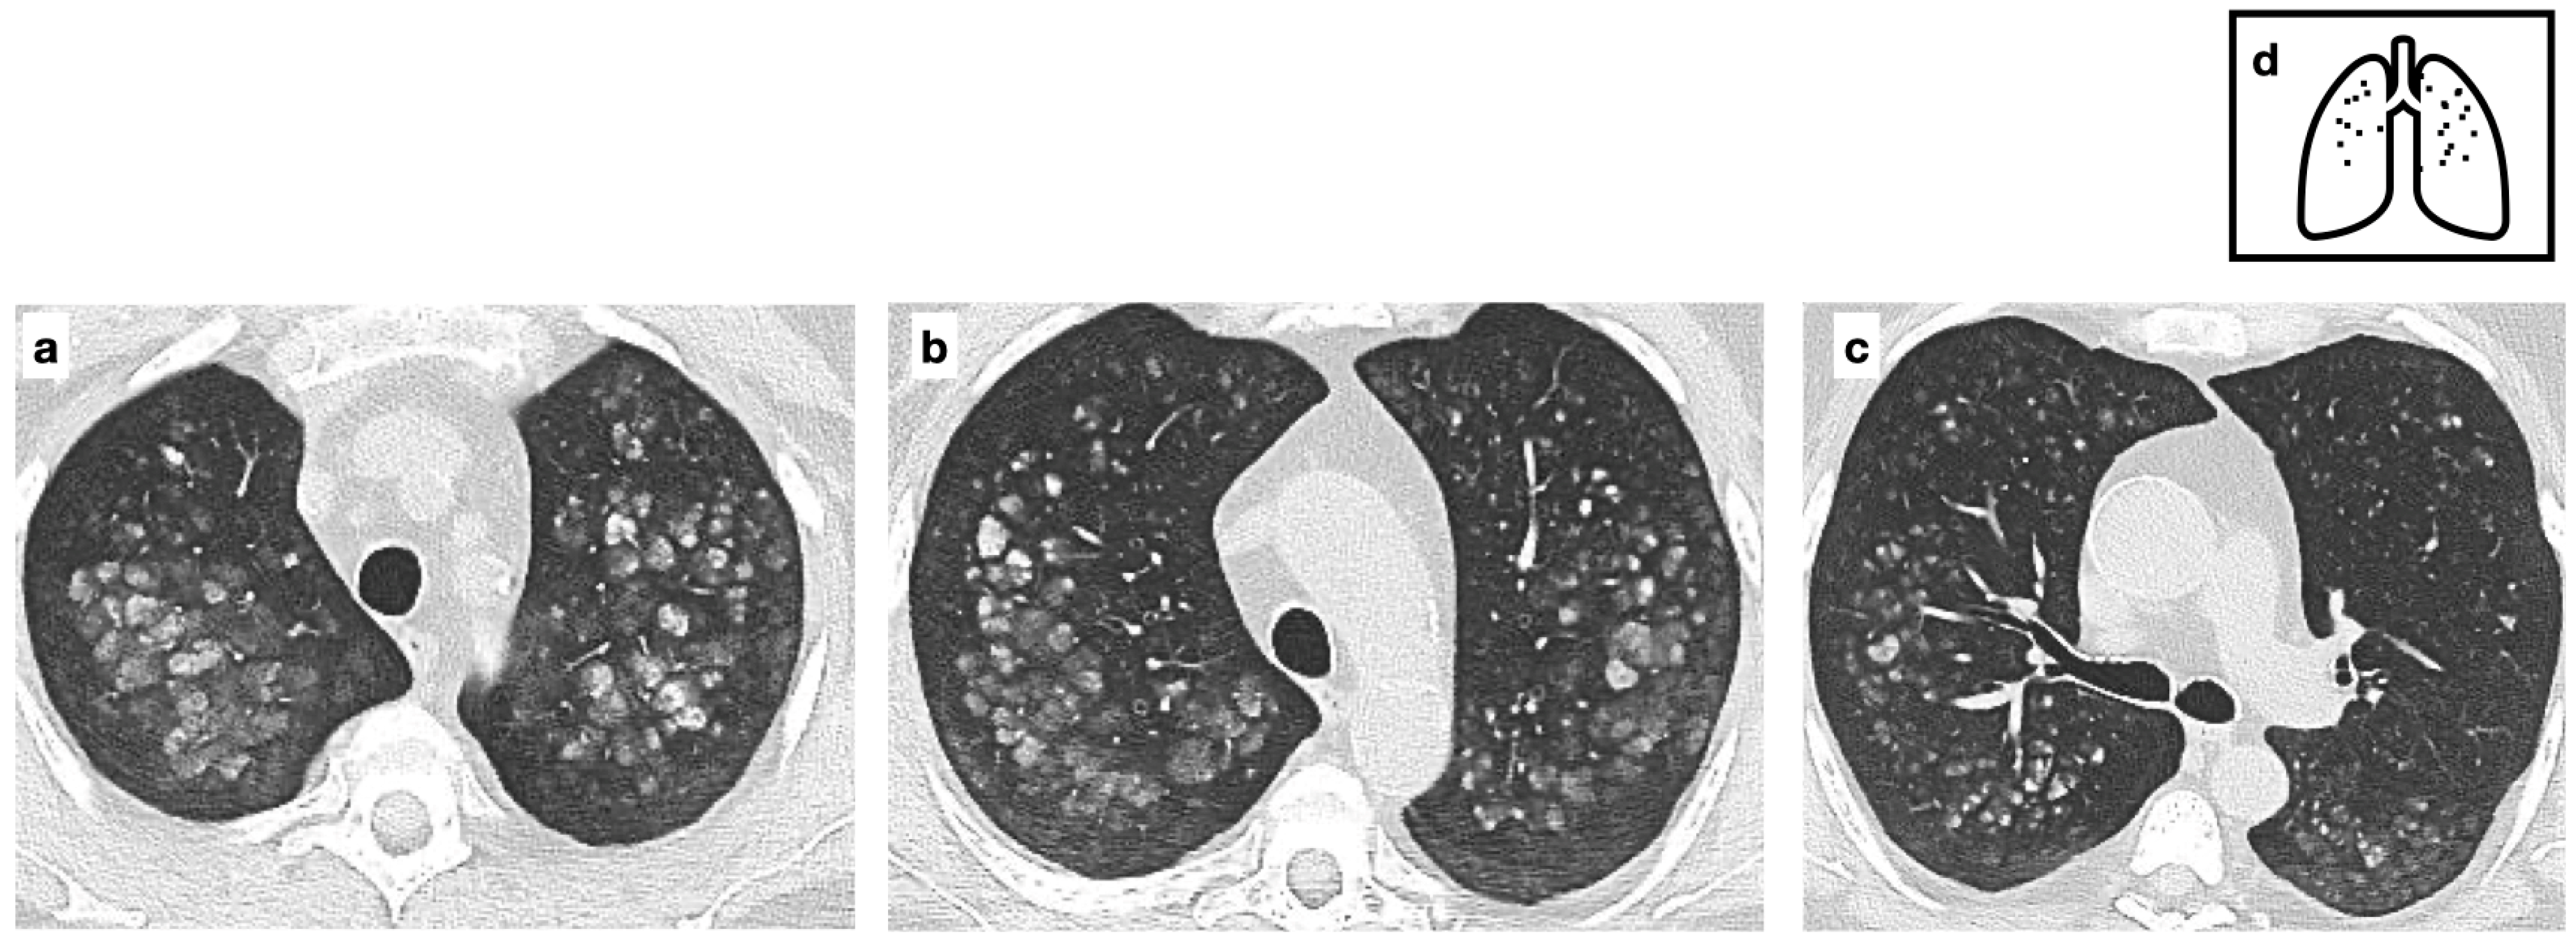

Figure 8.

Metastatic pulmonary calcification due to deposition of excess calcium in a background of normal lung parenchyma (a–c). These nodules are typically located in the upper lobes. HRCT images show fluffy centrilobular ground glass opacities, some of which calcified. Pattern of calcification (d). (Curtesy of E. Bezzon).

Regardless of etiology, MPC shows three CT patterns: (1) ground-glass opacities, (2) dense consolidation (often demonstrating intrinsic macroscopic calcium) and (3) a multinodular pattern consisting of numerous small, predominantly calcified nodules [25,26]. In this specific pattern, calcifications within the nodules correspond to calcium deposition in the alveolar walls and may appear as punctuate, ring-like, or diffuse. Due to the ventilation/perfusion ratio, alkalinity is higher in the upper lobes, where MPC predominantly occurs. Calcifications are frequently underdiagnosed because of microscopic deposition. in these cases, according to some Authors, Dual-energy CT with calcium suppression algorithm has proven useful in improving detection [27]. Nodules slowly develop over time and are often incidental findings in otherwise respiratory asymptomatic patients [28]. Calcifications of stomach, kidney and heart may be associated in these conditions. Particularly, calcification of the thoracic wall vessels is a frequent associated finding. On radiography, calcifications are rarely visible unless extensive. Conventional high-kVp techniques are suboptimal for their detection, whereas dual-energy digital radiography provides greater sensitivity than standard radiography [29]. On MRI, MPC with microscopic crystal deposition may appear hyperintense on T1-weighted images due to T1 relaxation time shortening, influenced by the surface area of calcium crystals. This effect can override the usual signal reduction caused by decreased proton density and altered T2 relaxivity. However, when calcium concentration exceeds 30–40%, T1 signal intensity progressively declines, restoring the typical appearance of signal voids or areas of reduced intensity [28,30].